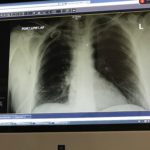

Check in, X-rays, pain meds. “It appears you have what is called a pneumothorax which is when a rupture occurs in your lung and air escapes into your chest cavity allowing your lung to deflate. You have a collapsed lung.”

Long story short (too late), I stayed in the hospital for two nights. In that lovely room with a nice view of Vail mountain, I had a tube inserted in my side that went between my lung and chest cavity to pull the air out between my lung and diaphragm. We had to reschedule flights back to the east coast and we were concerned about the pressure induced by flying. However the Vail Health Center docs assured us that planes are pressurized to around 7k feet. Vail is at approximately 8 thousand feet, so any stress induced by flying is not going to be as bad as what is occurring naturally at that altitude. However… don’t tell the airline this happened.